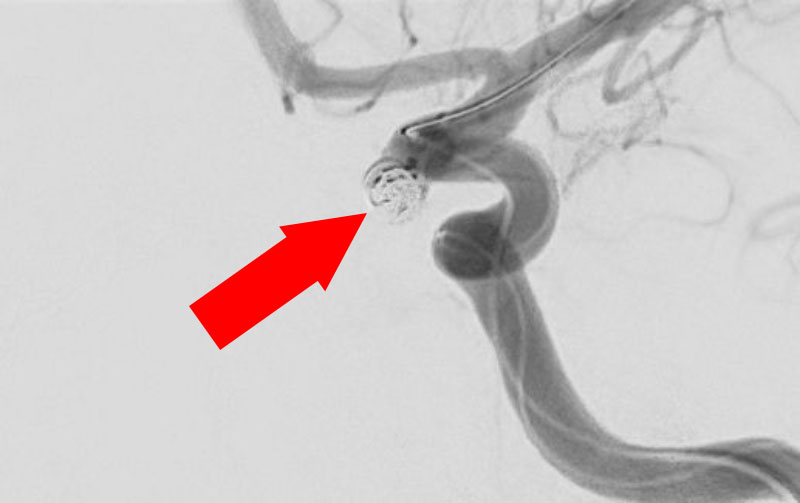

No.1631 手術後